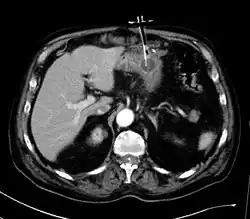

Mediante el ecógrafo se asegura que no haya anteposición del lóbulo hepático izquierdo y mediante la fluoroscopia se localiza el colon transverso.

El lugar óptimo de punción tiene que ser subcostal, aproximadamente entre el cuerpo y el antro gástrico equidistante entre las curvaturas mayor y menor.